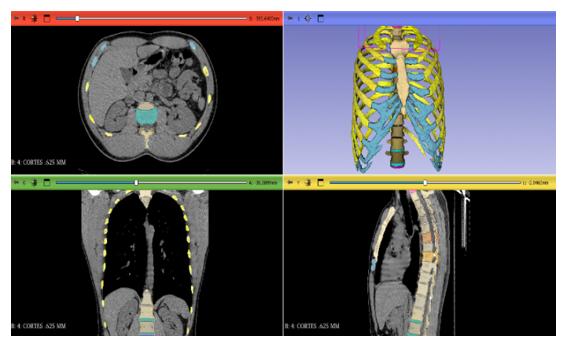

An observational and computational study was conducted to characterize the mechanical response of human ribs and their integration with the rib cage during physiological (quiet and deep ventilation) and non-physiological (vigorous coughing and external loads) scenarios. The methodological flow included: (1) medical image acquisition, (2) 3D segmentation and reconstruction, (3) geometric refinement, (4) meshing, (5) constitutive definition and material assignment, (6) boundary conditions and loads, (7) numerical solution and verification (Figure 1).

Figure 1 DICOM modeling in 3D slicer® software.

Image acquisition

Computed tomography (CT) scans of the chest (DICOM format) with appropriate slice thickness and FOV were used to define bone and cartilage geometry. When available, magnetic resonance imaging (MRI) was incorporated to refine costal cartilage and soft tissues. Equipment and protocol metadata (manufacturer, model, kVp/mAs, reconstruction kernel, slice thickness, MRI, and TR/TE sequences) were recorded. Data were anonymized prior to processing (Figure 2).